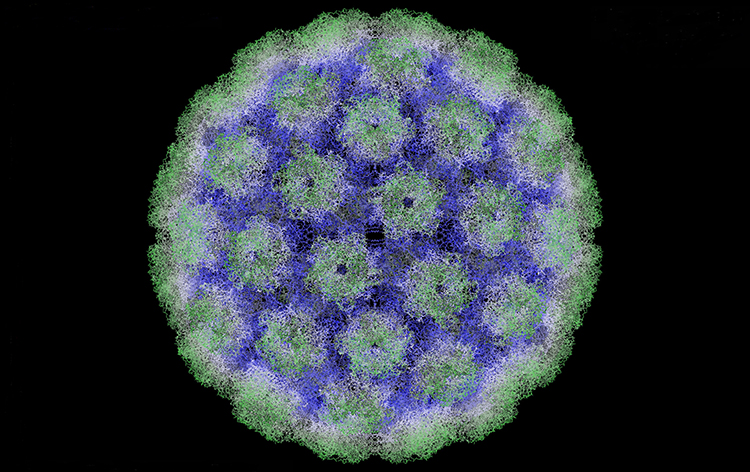

Virus-related cancers including cervical, anorectal and head and neck cancers associated with Human Papilloma Virus (HPV), Kaposi sarcoma and primary effusion lymphoma associated with Kaposi sarcoma-associated herpes virus, liver cancers associated with Hepatitis B and Hepatitis C viruses, and others are rapidly increasing in our region and disproportionately affect the African-American population. This increase may be explained in part by the large number of HIV+ patients in the region.